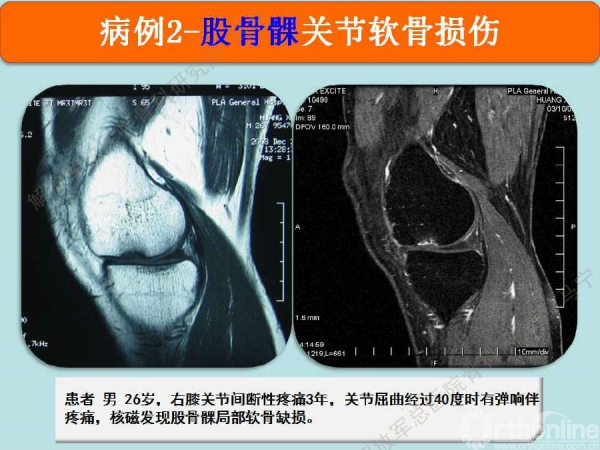

病例2

患者,男,26岁,右膝关节间断性疼痛3年,关节屈曲经过40度时有弹响伴疼痛,发现股骨髁局部软骨缺损。损伤的软骨下骨可见明显水肿。

切开后可以看见很明显的软骨破坏。

对糜烂的软骨进行清创,按照损伤的面积裁剪软骨补片进行修补。